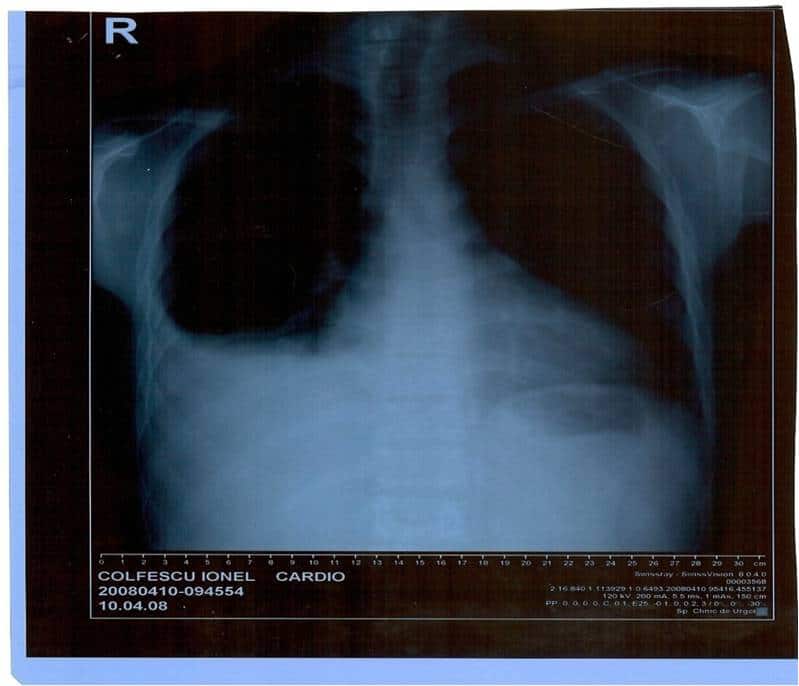

Rx toraco-pulmonar

Diagnostic prezumtiv

- Insuficienţă cardiacă predominent dreaptă, de cauză neclară

- Cardiomiopatie dilatativă?

Rx toraco-pulmonar (II)